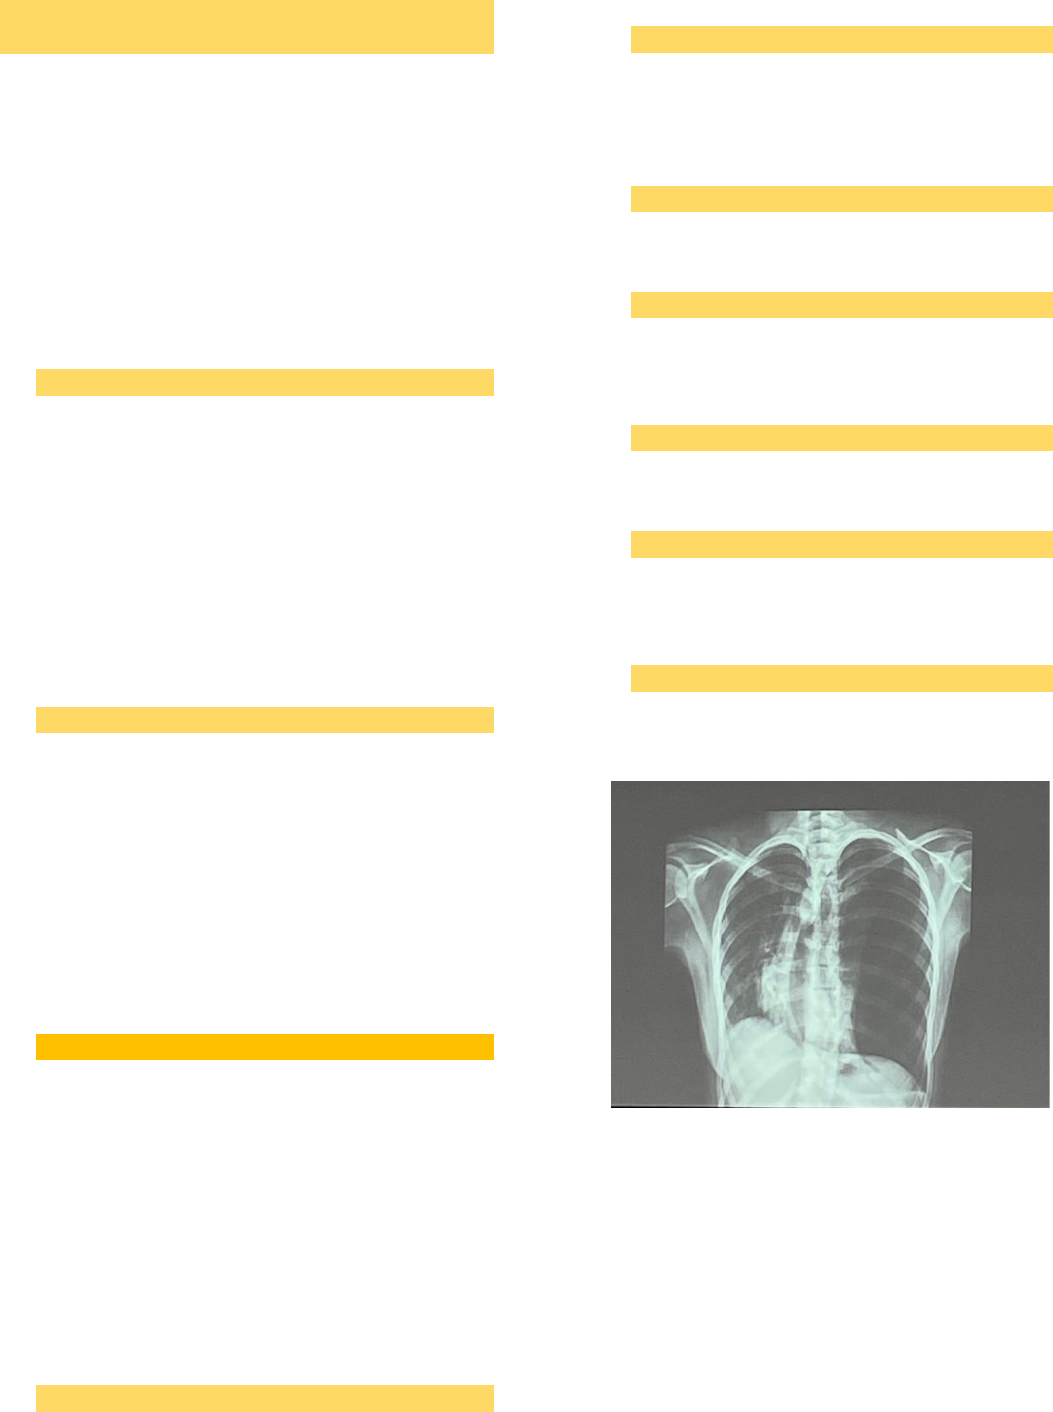

• Nesse imagem vemos: A – traqueia desviada para

a direita, brônquios fontes pérvios. B-hemitórax

esquerdo hipertransparente, apresentando

volume aumentado em relação ao hemitórax

direito, sinal da linha pleural evidente com

ausência da trama vascular lateralmente a linha

pleural evidente. Além disso temos atelectasia de

hemitórax esquerdo e alargamento dos espaços

intercostais. C-desvio contralateral do mediastino.

D-velamento do seio costofrênico a esquerda e

elevação do seio costofrênico a direita (indicando

aumento da pressão). E, F e G – sem alterações.

• Hipótese – PNEUMOTÓRAX

• Conduta: drenagem do hemitórax esquerdo – 5°

EIC, entre a linha axilar média e anterior (zona de

segurança), sempre na borda superior da costela

inferior